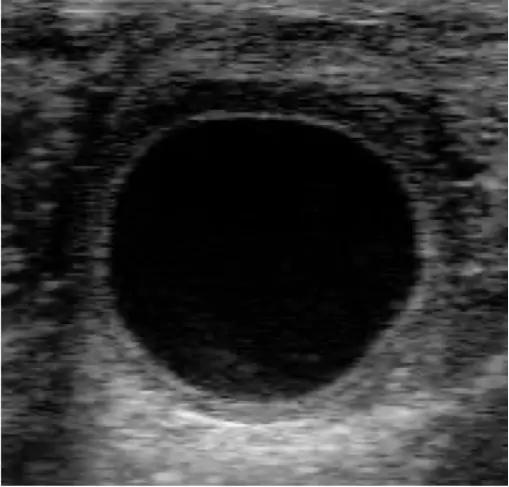

Гистологические изображения фолликулярной кисты яичника